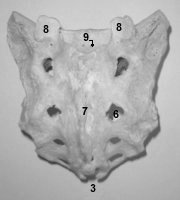

C'est un os médian, impair et symétrique de forme pyramidale aplatie d'AV en ARR et situé à la partie postérieure du pelvis (old. bassin). Il contribue à la formation de la ceinture pelvienne avec les 2 os coxaux.

Il est formé par la fusion de 5 vertèbres sacrées dont on peut encore différentier les reliefs des différentes structures. Il s'articule en HT avec la dernière vertèbre lombaire (par l'intermédiaire d'un disque intervertébral), latéralement avec les 2 os coxaux, en BAS avec le coccyx. Il possède 4 faces (ventrale / dorsale / latérales x2) et un sommet inférieur ou apex (3).

|

La

concavité

antérieure du sacrum est plus marquée chez l'homme. C'est un os plus court

et plus large chez la femme. Le sacrum possède des mouvements de nutation

et contre-nutation lors de l'accouchement (le sommet inférieur du sacrum

recule d'environ 2,5cm en fin d'accouchement alors même que les ischions

s'éloignent l'un de l'autre et que les ailes iliaques se rapprochent).

crête sacrée, la face postérieure.

face postérieure et l'apex (la pointe)